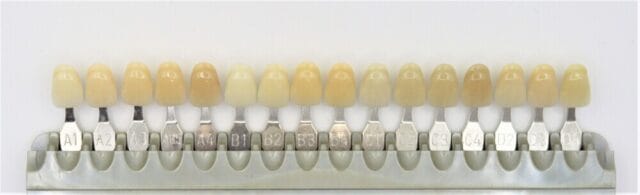

IMG_9945.jpg, メタルボンド | 取扱い技工物 | 歯科技工所 株式会社ジェネシス,

メタルボンド | 取扱い技工物 | 歯科技工所 株式会社ジェネシス, メタルボンドポーセレンブリッジ(MB Br)が出来るまで,

メタルボンドポーセレンブリッジ(MB Br)が出来るまで,![歯周病治療③] メタルボンドブリッジ補綴で咬合機能の回復|(医 歯周病治療③] メタルボンドブリッジ補綴で咬合機能の回復|(医](https://seimitsushinbi.jp/wp/wp-content/uploads/2017/12/73d89cac71be0e4af02e7707131c0309.jpg) 歯周病治療③] メタルボンドブリッジ補綴で咬合機能の回復|(医,

歯周病治療③] メタルボンドブリッジ補綴で咬合機能の回復|(医, メタルボンドポーセレンブリッジ(MB Br)が出来るまで,

メタルボンドポーセレンブリッジ(MB Br)が出来るまで, メタルボンド チタンボンド - 株式会社足利セラミックラボラトリー,

メタルボンド チタンボンド - 株式会社足利セラミックラボラトリー, メタルボンド | 東京都あきる野市きらら歯科【年中無休】,

メタルボンド | 東京都あきる野市きらら歯科【年中無休】, メタルボンド | 東京都あきる野市きらら歯科【年中無休】,

メタルボンド | 東京都あきる野市きらら歯科【年中無休】, メタルボンドポーセレンブリッジ(MB Br)が出来るまで,

メタルボンドポーセレンブリッジ(MB Br)が出来るまで, 左下メタルボンドブリッジを除去しました。2018.01.24|広島市南,